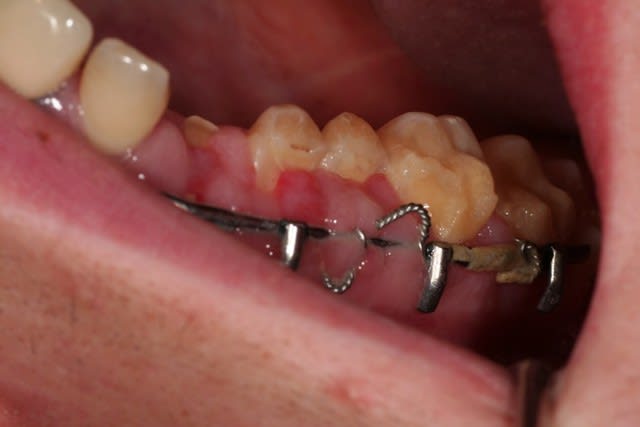

pas le temps de faire des commentaires ce matin, je balance le cas, et lâchez vous

donc, effectivement, un gros choc avec fractures multiples. effectivement marco, c'est un cas long mais qui n'a rien de sorcier en soi, je l'ai posté parce qu'il étendu et impressionnant.

je n'ai rien entrepris pour l'instant parce que l'ouverture buccale est très limitée, et je voudrais que le maxillo débarrasse le patient de toute la ferraille avant de commencer.

pour l'instant j'en suis à concevoir une approche, et je bute sur 36 et 37: endo + élongation + ccm, ou alors extraction? je crois que la 36 va sauter, mais 37 m'embête.

autre chose qui m'embête, c'est d'être obligé d'attendre la dépose des mini-plaques avant de pouvoir implanter 23 , 24 et 13.